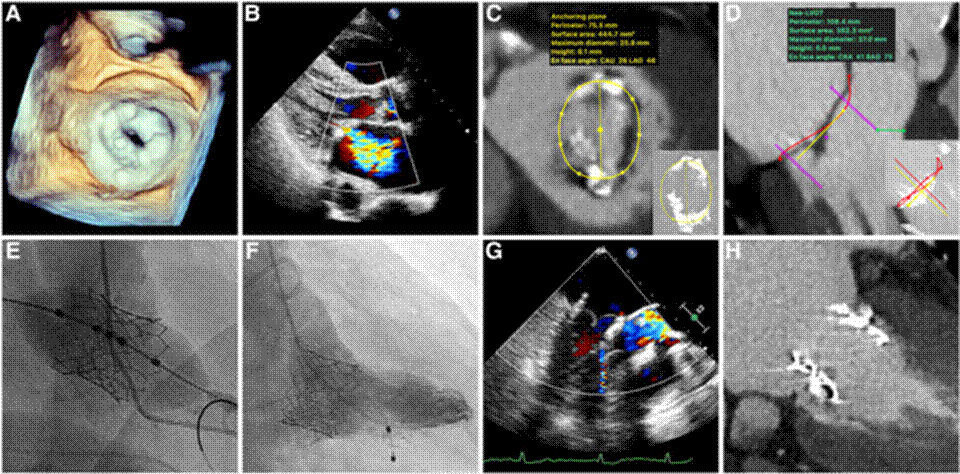

3. 瓣膜病介入治疗技术

2022年,四川大学华西医院陈茂教授团队使用国产自主研发的PrizvalveR介入瓣膜为一例外科手术极高危的风湿性二尖瓣狭窄患者成功实施经导管二尖瓣植入,这是国际首例在风湿性二尖瓣狭窄患者中通过植入球扩式介入瓣膜实现二尖瓣功能替换。相关成果2022年8月发表于《European Heart Journal》。

四川大学华西医院陈茂团队-瓣膜病介入治疗技术 四川大学华西医院陈茂团队-瓣膜病介入治疗技术